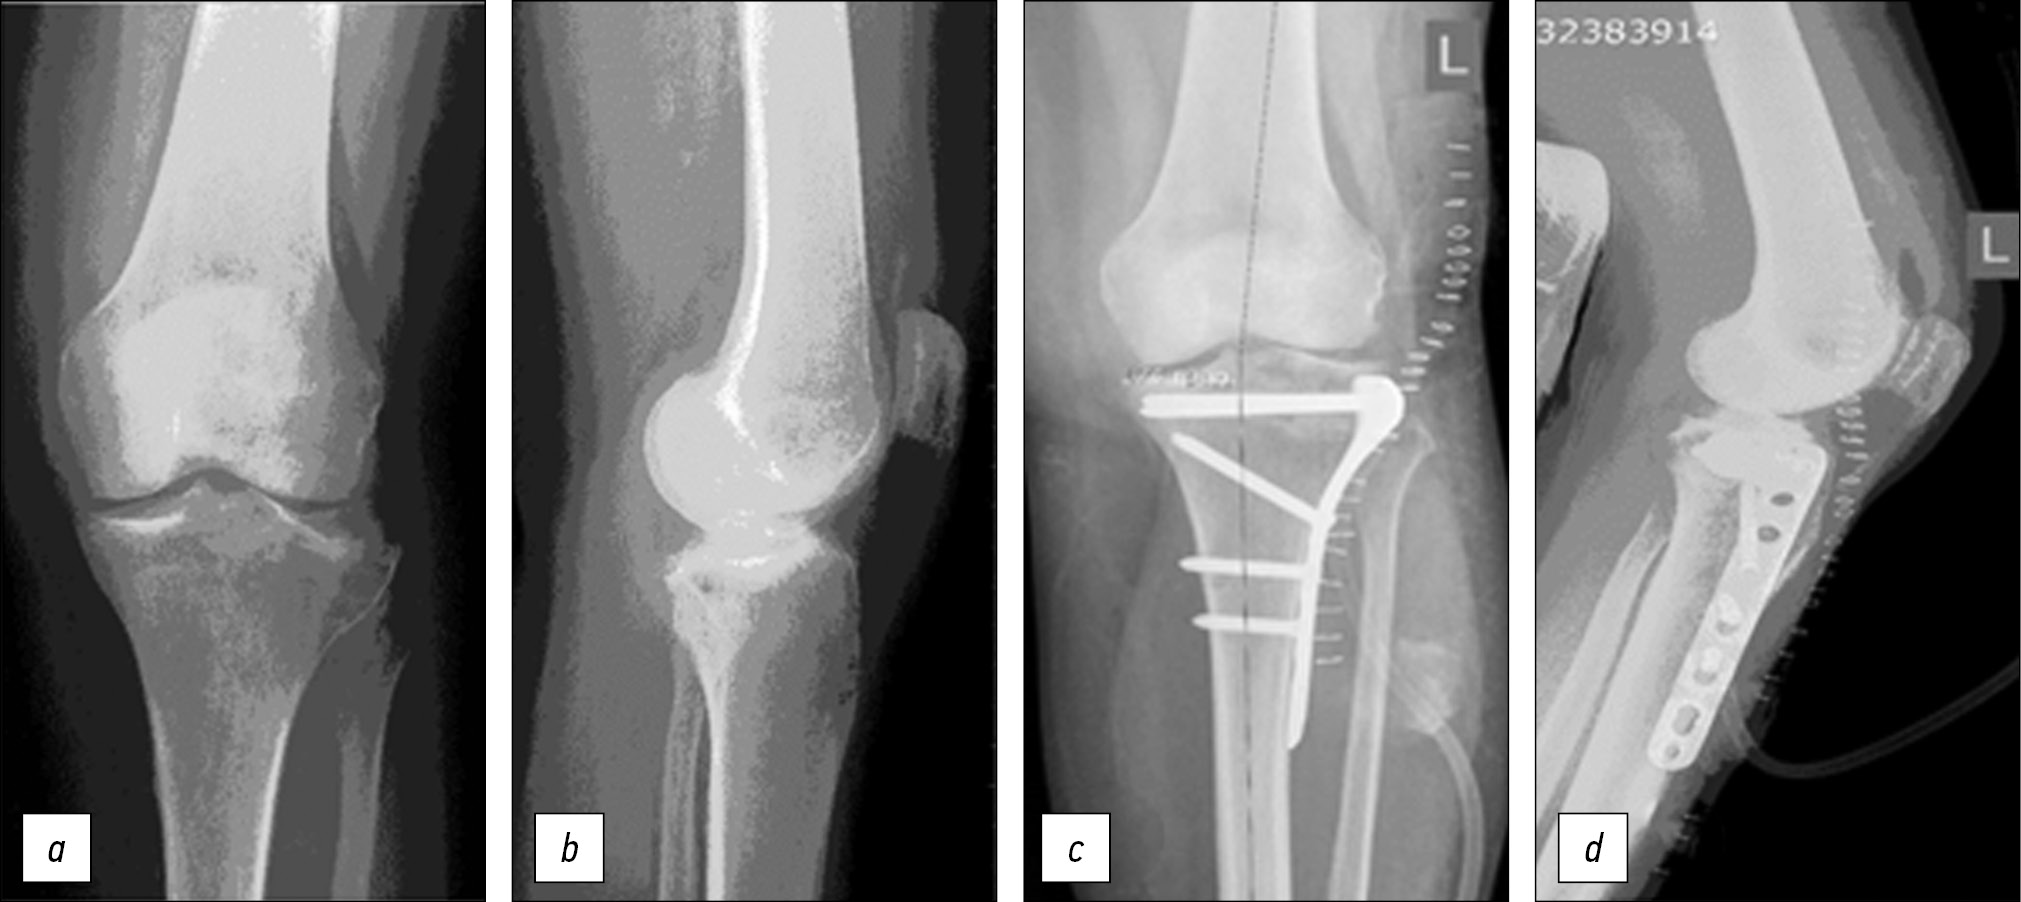

Surgical technique. In the case of valgus deformity, intra-articular osteotomy of displaced osteocartilaginous fragments with bone defect replacement with an allograft and fixation with locking compression plate proximal tibia plate was most often performed (n=25) (Fig. 1).

Figure. Radiographs of the knee joint of a 65-year-old female patient: a, b — on admission: malunion of the proximal tibia fracture. On radiographs of the knee, valgus deformity with impression of the lateral condyle of the tibia was determined; c, d — intra-articular osteotomy of the posterior and central part of the lateral condyle was performed, osteotomy and reduction of the osteochondral fragment, filling of the bone defect formed during the elevation of the articular surface with an allograft, fixation with an LCP PTP. The congruity of the articular surface was restored, the deformity was corrected.